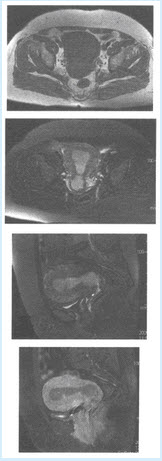

(单选题)该患者的CT所示,结合病史,该患者最可能的诊断是()

A:肺脓肿

B:肺癌

C:炎性假瘤

D:肺结核

E:转移瘤

F:大叶性肺炎

(单选题)本病最可能的病理类型为()

A:腺癌

B:小细胞癌

C:大细胞癌

D:鳞癌

E:鳞腺癌

F:以上都不是